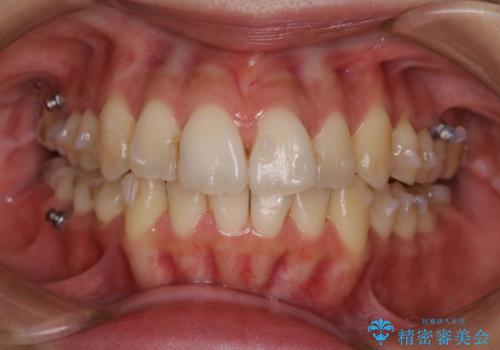

- 元の色は普通より少し黄色めの白さでした。お口の中は、プラーク等付着してなくてきれいな状態でした。

ホワイトニングエクセレントコースで3回照射の施術をしました。